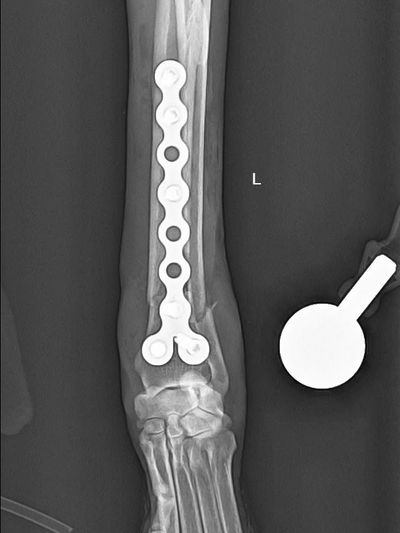

Our veterinary orthopaedics unit specializes in diagnosing and treating bone, joint, and ligament conditions in dogs and cats.